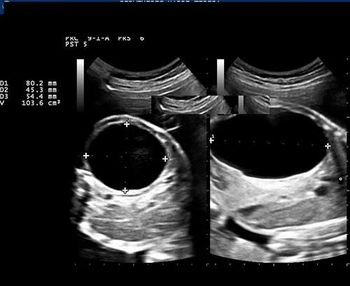

This image quiz focuses on the kidneys. Can you identify the abnormality seen in these ultrasound images of the fetal abdomen?